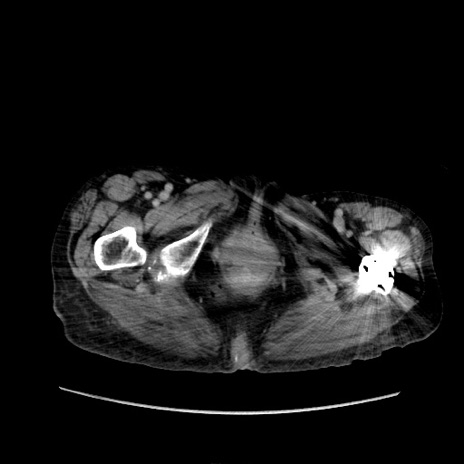

症例31(横断像)

【症例】80歳代 女性

【主訴】腹部膨満感

【現病歴】他院にて肝硬変にてフォロー中。1週間前から便秘、腹部膨満感、臍部腫瘤あり受診となる。

【既往歴】肝硬変

【身体所見】腹部膨隆あり、皮膚変化なし、疼痛なし。

【データ】WBC 4600、CRP 0.25